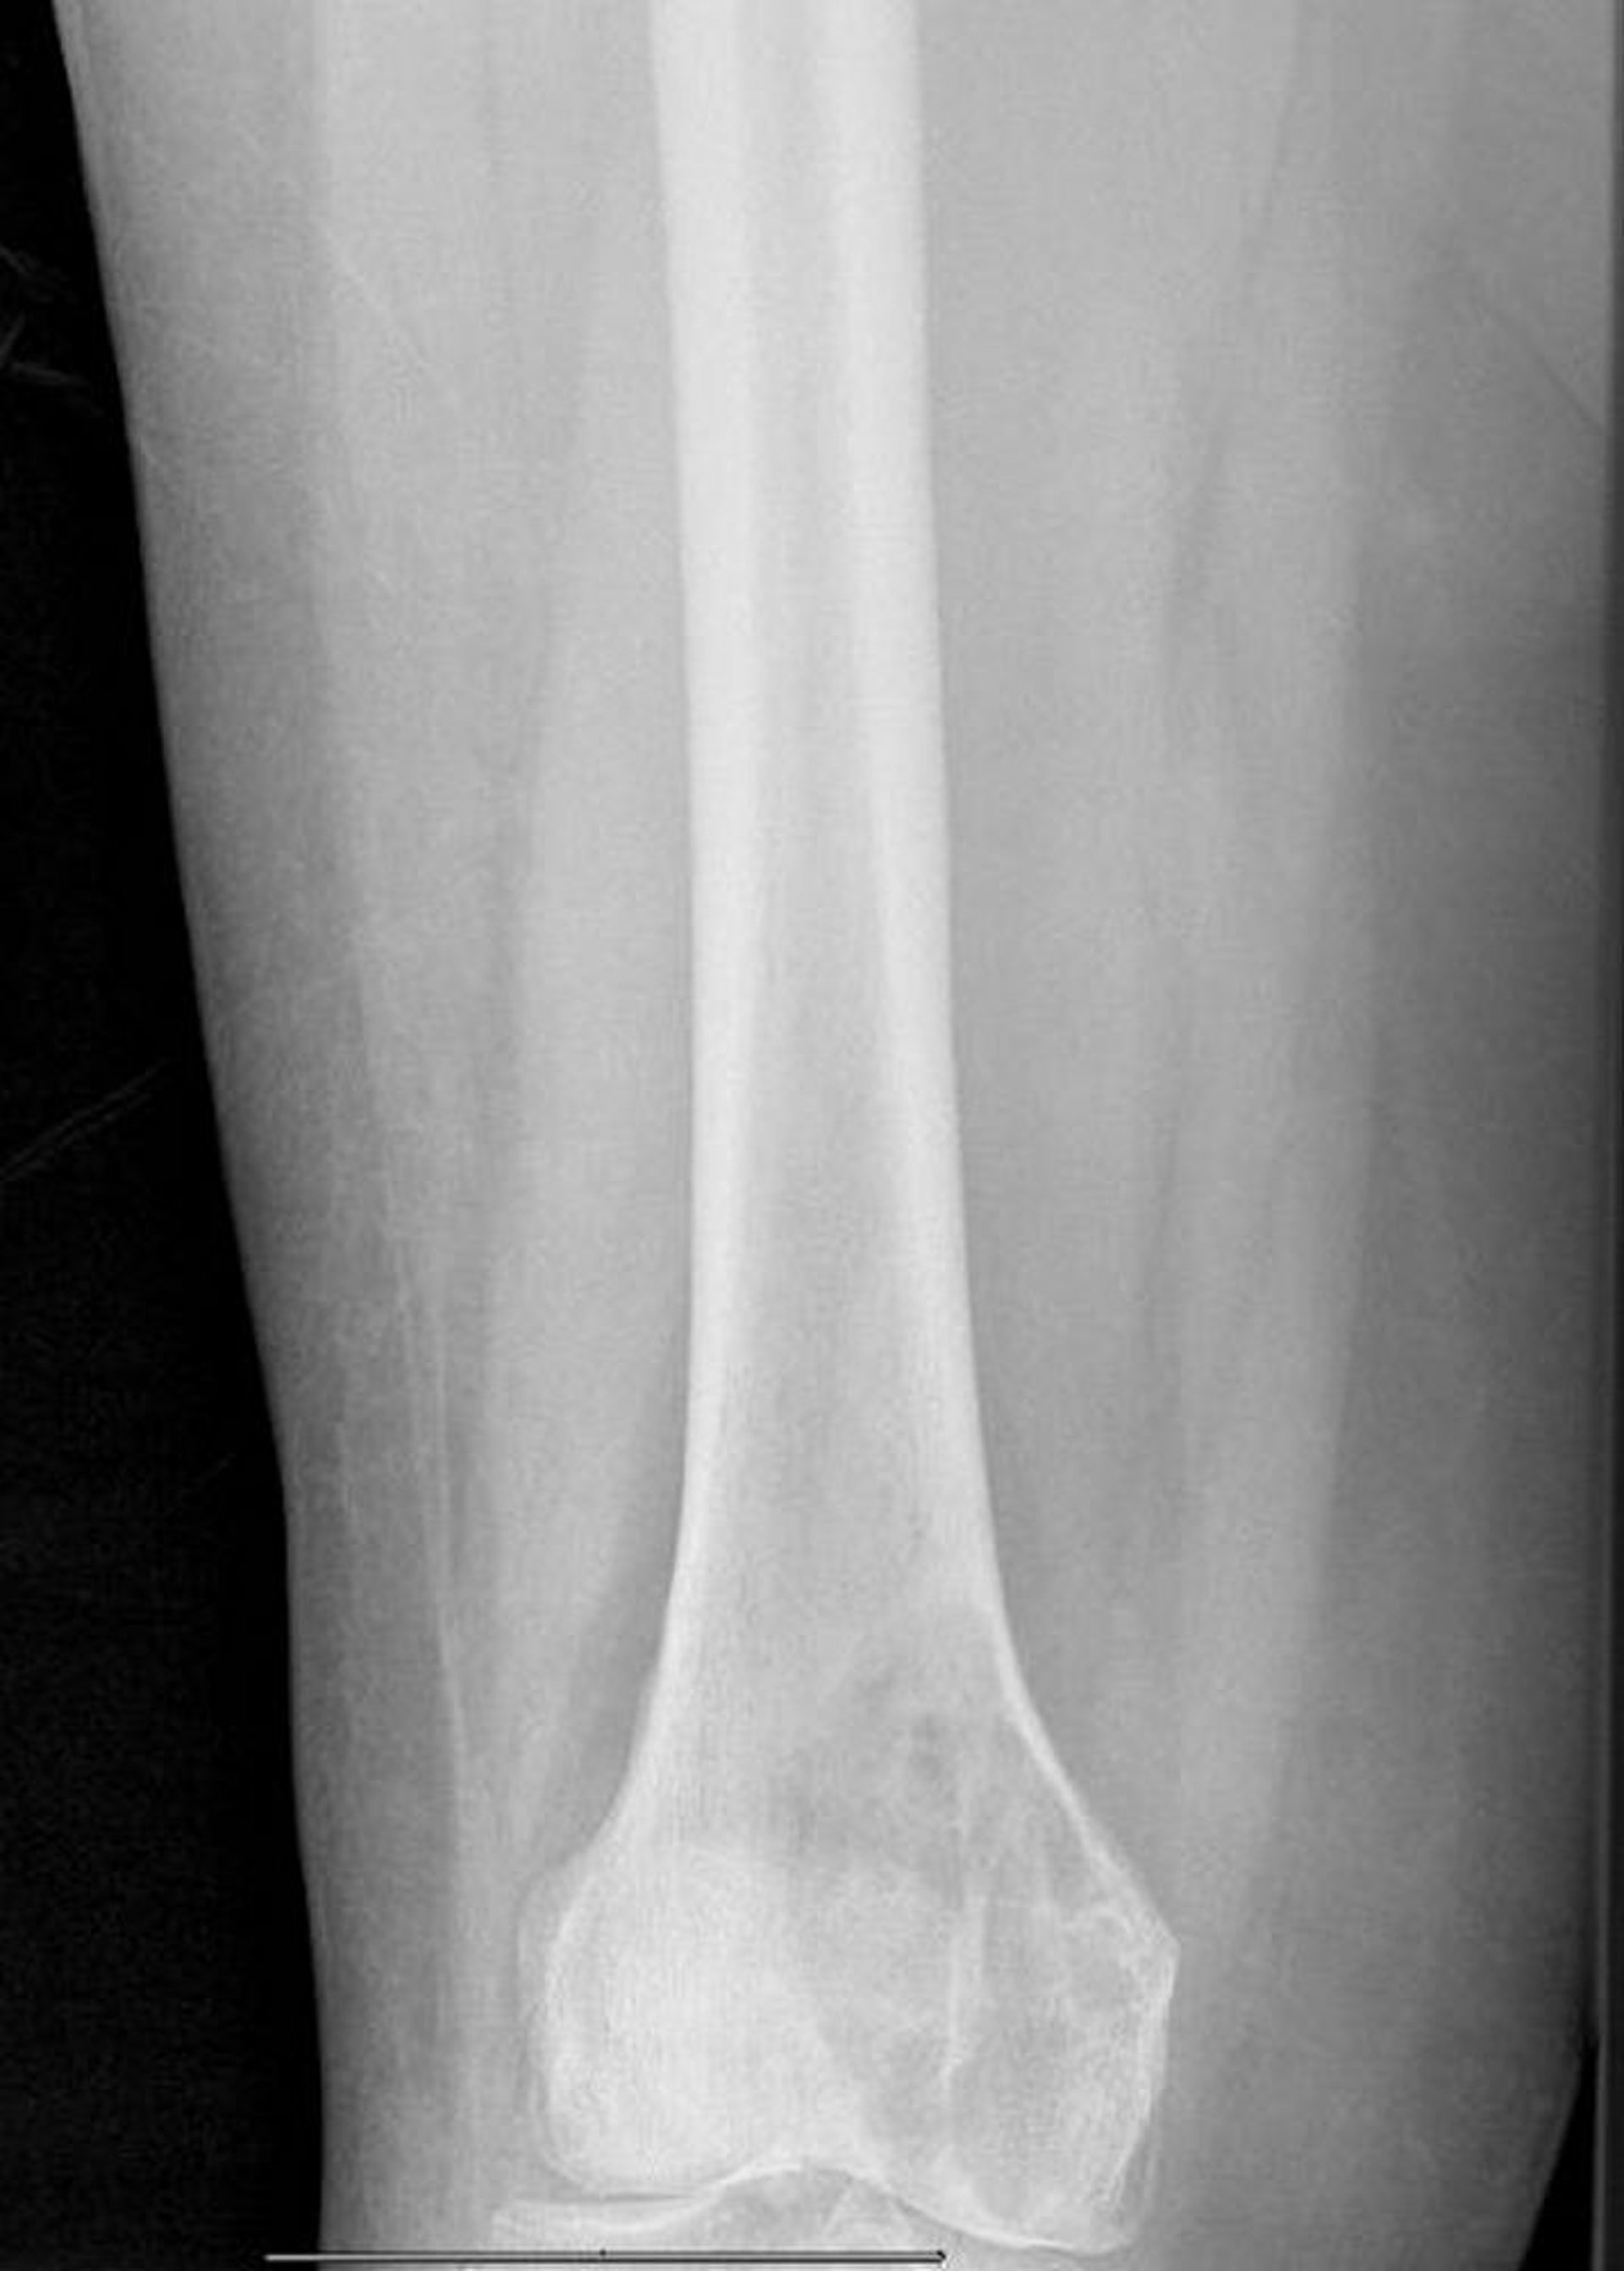

Phim chụp X-quang này cho thấy tổn thương tiêu xương do di căn lớn ở lồi cầu trong xương đùi với nguy cơ gãy xương bệnh lý.

Hình ảnh do bác sĩ Michael J. Joyce và bác sĩ David M. Joyce cung cấp.